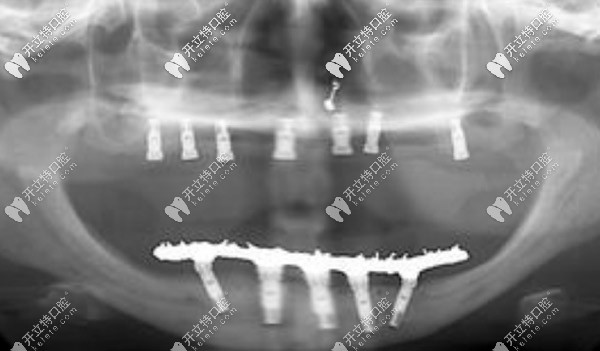

【全口allon4/6即刻負(fù)重技術(shù)】

一般需要8顆或12顆種植體,可恢復(fù)全口牙,當(dāng)然這個(gè)費(fèi)用比較高,韓系的價(jià)格一般在12萬(wàn)元起。

滿口allon4/6即刻負(fù)重技術(shù)

種植牙的優(yōu)勢(shì)就不過(guò)多介紹了,ALLon4與普通的種植技術(shù)不同在于,利用斜拉式的力學(xué)原理,可以避免上頜竇及下頜神經(jīng)等危險(xiǎn)區(qū),當(dāng)天即可戴牙吃東西。美中不足則是該技術(shù)對(duì)醫(yī)生的技術(shù)要求較高,且費(fèi)用較高。